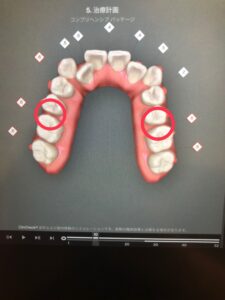

矯正中は、歯を動かしていく過程で下の写真のように隙間ができます。

こういった隙間は普通の歯ブラシだと届きにくいため、ワンタフトブラシとフロスを使って念入りに磨いていきます。